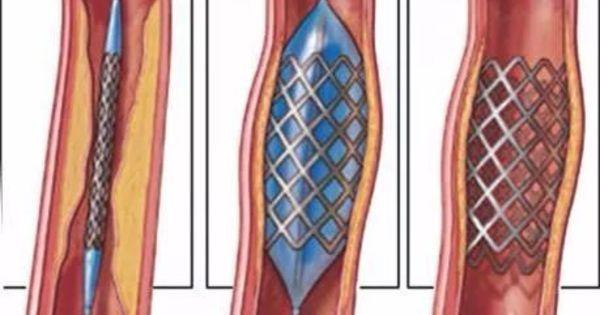

●Thérapie endovasculaire :Une sténose sévère des gros vaisseaux (artères carotide interne, cérébrale moyenne, basilaire) est donnée.Stenting endovasculaire (pour recirculer le flux sanguin)或Endartériectomie carotidienne (élimination de la plaque et des dépôts graisseux)。